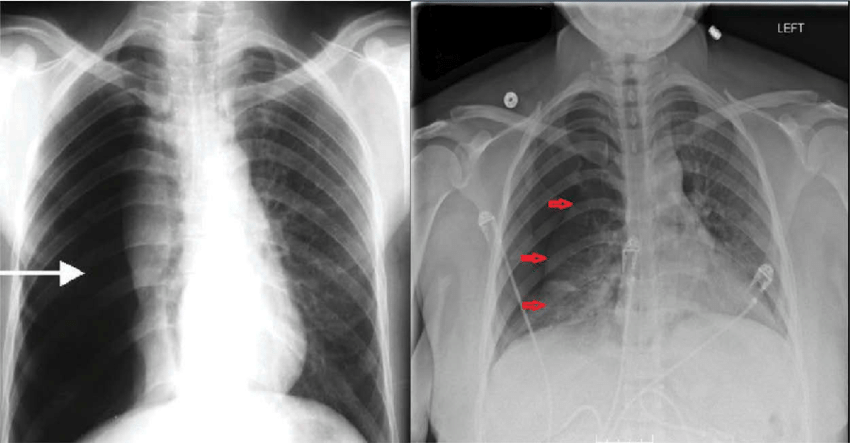

심각한 경우

- 치료 방법: 흡인 또는 흉관 삽입

재발성 기흉

- 치료 방법: 흉막유착술, 수술적 치료